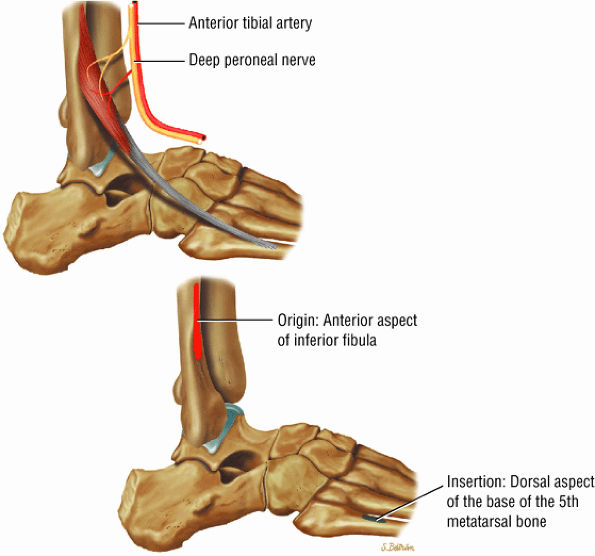

The anterior muscles of the leg are the tibialis anterior (Fig. 5.2), the extensor hallucis longus (Fig. 5.3), the extensor digitorum longus (Fig. 5.4) and the peroneus tertius (Fig. 5.5).

FIGURE 5.5 ● PERONEUS TERTIUS The peroneus tertius represents a lateral slip of the extensor digitorum longus. Isolated ruptures of the peroneus tertius tendons do not occur. The peroneus tertius dorsiflexes and everts the foot.